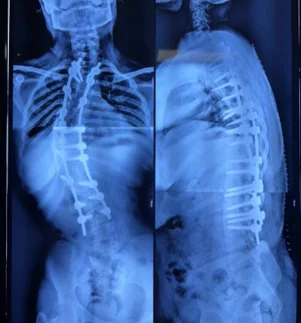

Before & After Clinical Gallery

We showcase real patient cases (with consent), including:

- Pre- and Post-operative MRIs and X-rays

- Disc Herniations, Stenosis, and Spondylolisthesis cases

- Visible improvement in alignment and decompression